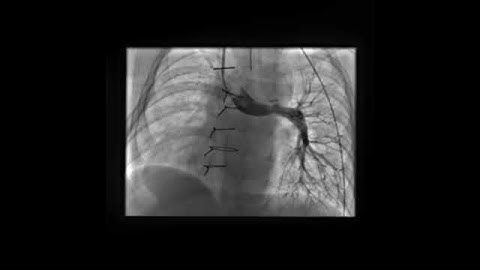

LV Angiogram in LAO Cranial view profiling a high muscular VSD